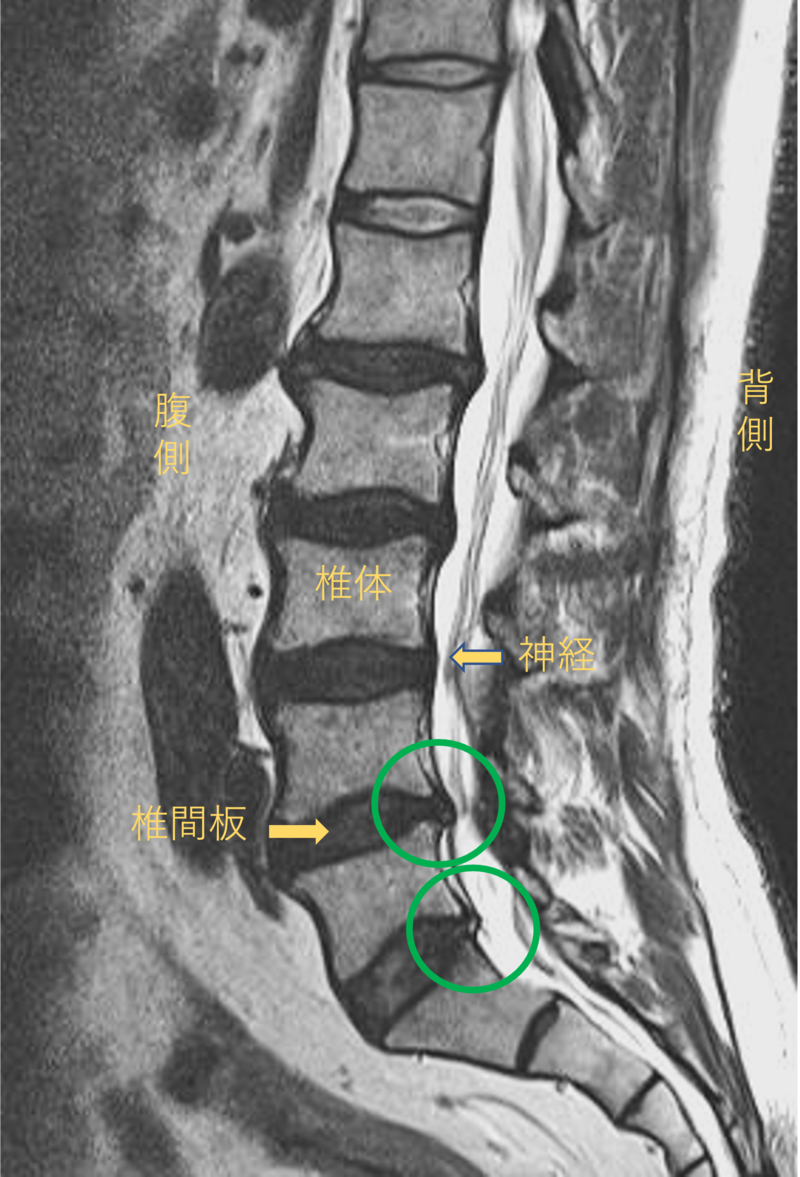

腰を横から見たMRI画像です。

腰椎という骨と骨の間に椎間板と呼ばれるクッションがあります。

このクッションの中身が飛び出す状態が椎間板ヘルニアと呼ばれます。

このMRI画像では、椎間板が背中側に飛び出して足に向かう神経が圧迫されることが痛み、しびれの原因となっておりました。